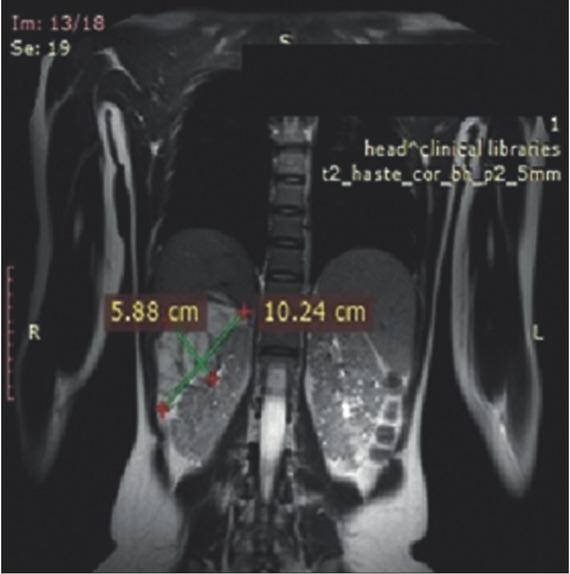

Figure 2